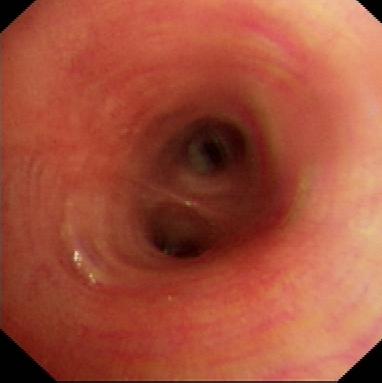

病例1:结核所致右主支气管瘢痕性狭窄

病例2 恶性肿瘤所致气管狭窄

理结果:鳞癌.